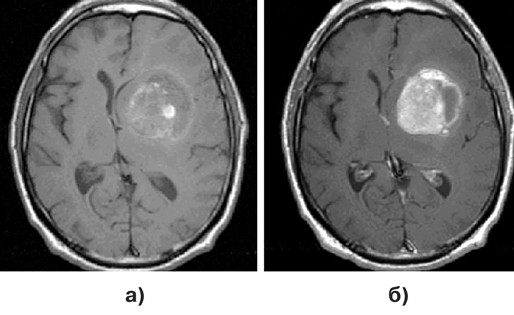

Диагноз подтверждается при МРТ, причем для визуализации небольших метастазов исследование целесообразно выполнять сразу с контрастированием препаратом гадолиния. Обычно метастазы выглядят как зоны повышенного сигнала как в Т1, так и Т2 режимах МРТ (рис. 1–3).

Рисунок 2. Метастаз меланомы в лобно-височную область слева, МРТ (Т1 режим) без (а) и с контрастным (б) усилением, аксиальная проекция